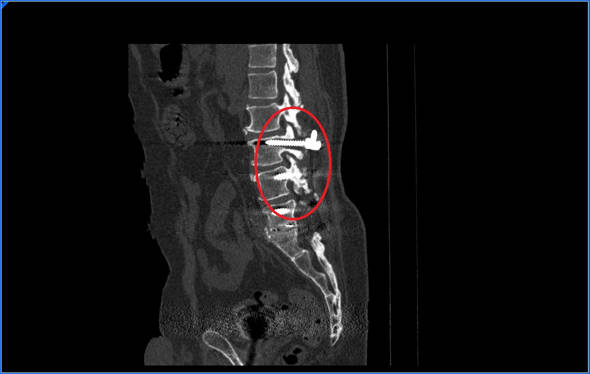

La prueba que mejor nos permite observar que no hay puentes óseos que crucen de una vértebra a otra es el TAC.

La cirugía consiste en aumentar la estabilidad de la zona intervenida, bien introduciendo una caja intersomática si no la había o ampliando el diámetro de los tornillos si estos estaban aflojados.